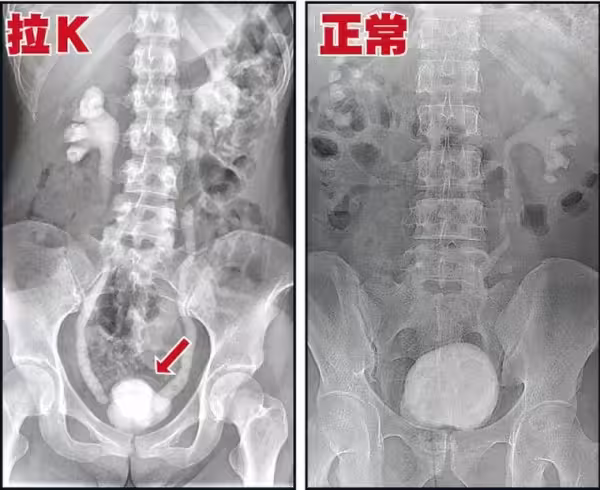

高醫泌尿部主治醫師錢祖明強調,

K他命對膀胱黏膜的傷害是不可逆、

無法恢復的,「醫界能做的很有限」。

其實吸食K他命長久的人,必然會有這種尿頻、尿急、尿痛的症狀,

這是由於K他命的獨特性,持續傷害人體的泌尿系統,導致的嚴重後果。

K他命是一種結晶、有稜角的固體物質,

從鼻子吸入,然後進入呼吸系統、消化系統,

其中約有5%的K他命原型會經泌尿系統的尿道排出。